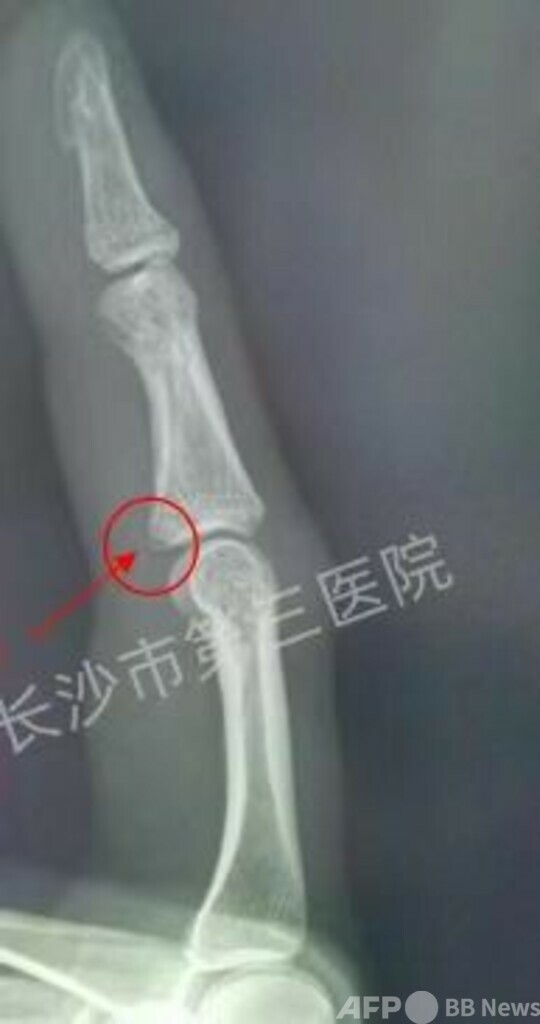

李さんは最近、左手の人差し指が腫れ、痛みが止まりませんでした。病院で検査を受けると、なんと人差し指の中節骨の脆弱性裂離骨折でした。

検査した放射線科の医師が李さんに最近けがしたかどうかを尋ねましたが、李さんは否定しました。しかしよく考えると、前日の夜に蚊に刺され、手を振って蚊をたたこうとしたことを思い出しました。手は蚊に当たりませんでしたが、強く振ったため指が痛くてたまりませんでした。

医師の診察によると、今年35歳の李さんは甲状腺がんの根治手術を受けたことがあります。術後、長期にわたって治療薬のユーシロクスを服用していました。そして、骨密度検査で、李さんの骨量が減少していることが分かりました。医師は、骨量の減少で骨がもろくなっているため、蚊をたたくという日常の小さな動作でも骨折する可能性があると指摘しました。

医師は李さんの人差し指の中節骨をシーネで固定し、カルシウムの服用と日光に当たってカルシウムを補給するようアドバイスしました。(c)CGTN Japanese/AFPBB News